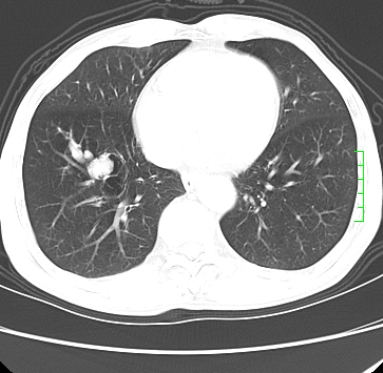

m,73y。膝关节疼痛伴双下肢水肿。入院常规胸片发现结节灶。增强为静脉期。

浅分叶、棘突,考虑右下肺周围型肺癌

考虑周围型肺癌  ,双上肺结核。

肿块周围可见局限性气肿,考虑肺癌可能性大。双肺上叶继发型肺结核。

指套征,强化明显,近侧肺组织局限性肺气肿,考虑支气管类癌,慢支、肺气肿、双上陈旧性tb、冠脉钙化。

鉴别:先天性支气管闭锁,变态反应性支气管肺曲霉菌病,肺癌,支气管囊肿,支扩黏液嵌塞。

1)考虑右肺下叶周围型肺癌。2)右肺上叶及左肺感染性病变(结核可能)。3)肺气肿。4)冠状动脉钙化。